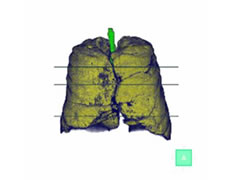

胸部CT検査:9,900円(税込)

胸部レントゲンではわかりづらい小さな病変を映し出すことが可能で、肺がんを発見するのに役立つ検査です。

肺気腫検査(ラングビジョン)

肺気腫はおもにたばこが原因で、正常な肺胞が破壊される恐ろしい病気です。

肺全体のCT画像を解析し、肺気腫の部分を抽出してその状態や程度をより高い精度で評価する検査です。

胸部CT検査 + 肺気腫検査 12,100円